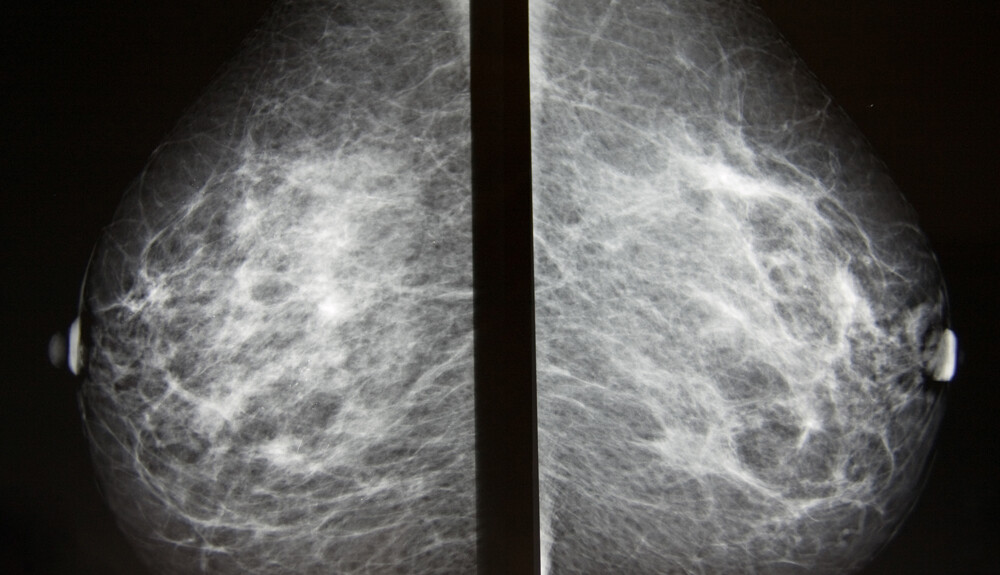

Pri mamografii sa z prsníkov snímajú röntgenové snímky. Tieto snímky je možné použiť pri skríningu rakoviny prsníka alebo na diagnostické účely, napríklad na vyšetrenie určitých príznakov či nezvyčajných nálezov zistených inými zobrazovacími metódami.

Počas snímania sa prsník pritlačí medzi dve pevné platne, aby sa prsné tkanivo rozprestrelo. Potom sa pomocou röntgenu vytvoria čiernobiele snímky, ktoré sa zobrazia na obrazovke počítača a vyšetrujú sa na prítomnosť znakov poukazujúcich na nádorové ochorenie. Snímky sa zhotovujú na prístroji špeciálne určenom na mamografiu. Pre dosiahnutie dobrej kvality obrazu a súčasné zníženie ožiarenia sa prsníky – jednotlivé – stláčajú pomocou špeciálnych plastových dosiek a následne sa zhotovujú dvoj smerné röntgenové snímky. Tradičné mamografické vyšetrenie vo všeobecnosti nie je bolestivé, avšak stláčanie prsníkov môže byť nepríjemné. Technik vám pomôže nastaviť hlavu, ruky a trup tak, aby prístroj mohol prsník bez problémov oskenovať.

Pri mamografii, ako už bolo spomenuté, sa robia čiernobiele snímky prsného tkaniva. Ide o digitálne snímky, ktoré sa zobrazia na obrazovke počítača a rádiológ ich vyhodnocuje.

Rádiológ hľadá známky, ktoré by poukazovali na nádorové zmeny, a iné stavy, ktoré môžu vyžadovať ďalšie vyšetrenia, sledovanie alebo liečbu.